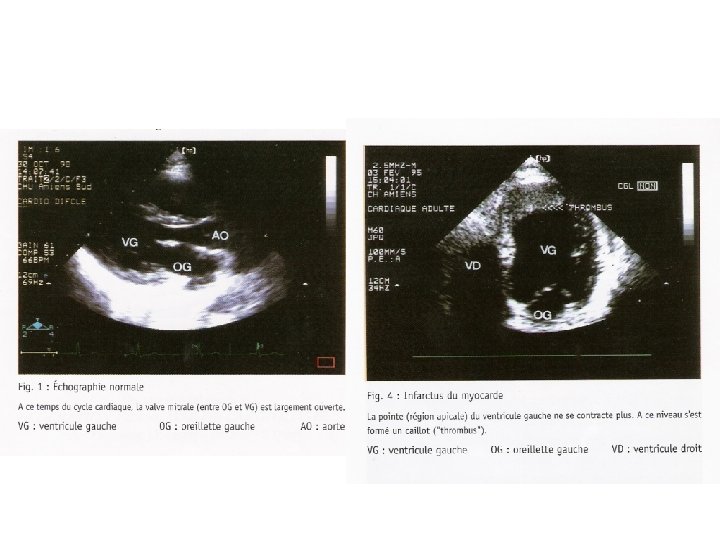

2. Echographie Doppler L’échographie est une technique d’exploration de l’intérieur du cœur par des ultras sons. Le médecin place une sonde sur la poitrine du patient qui est torse nu et allongé sur le coté gauche. La sonde envoie un faisceau d’ultra son dans la zone à explorer. Selon la nature des tissus, ces ondes sont réfléchies avec plus ou moins de puissance. Ces échos sont analysés en temps réel par l’ordinateur intégré à l’échographie, qui en déduit la forme et les mouvements du cœur. C’est un examen indolore qui permet d’observer la contraction du muscle cardiaque et les mouvements des valves.

Avantages du Doppler : • court 15 à 30 mns et décisif, • observer la circulation du sang au sein des cavités cardiaques et à travers les valves, • mesurer avec précision la vitesse d’écoulement du sang, • surveiller les valves artificielles